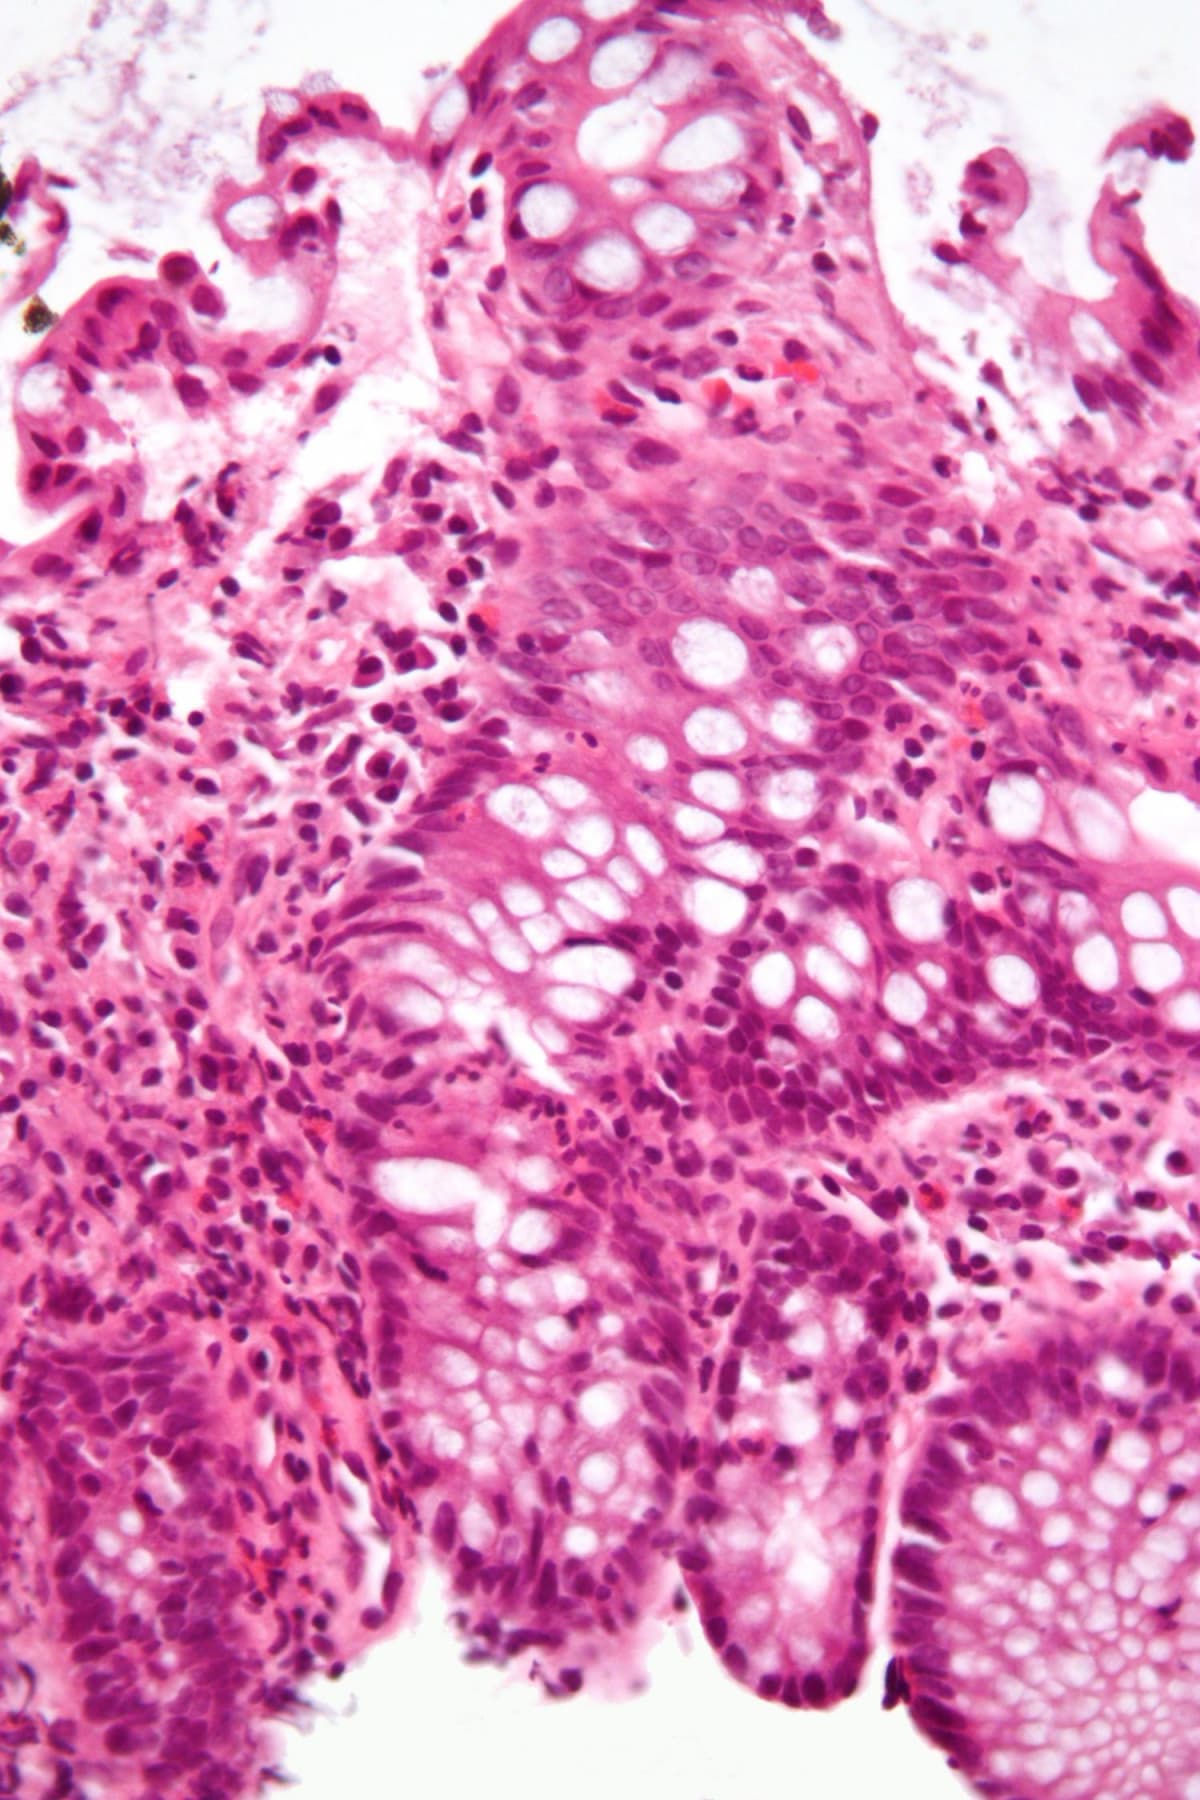

The blood mutations essentially "supercharge" inflammation in the gut, making conditions like Crohn's disease and ulcerative colitis much worse. Between 2.4 and 3.1 million Americans live with these painful diseases, with rates highest in people over 45.

"A single, oral drug that's already known to be safe in humans could reverse nearly all of the harmful effects," said lead researcher Dr. Ramesh Kumar. The drug reduced inflammation and restored colon health without weakening the immune system like current treatments do.

Current IBD treatments often suppress the entire immune system, leaving patients vulnerable to infections. This new approach targets only the problematic inflammation pathway, offering a smarter, safer option.